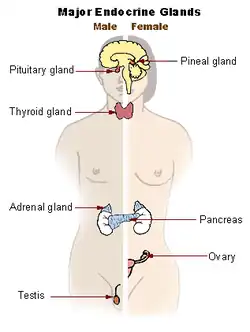

Hypopituitarism is the decreased (hypo) secretion of one or more of the eight hormones normally produced by the pituitary gland at the base of the brain.[1][2] If there is decreased secretion of one specific pituitary hormone, the condition is known as selective hypopituitarism.[3] If there is decreased secretion of most or all pituitary hormones, the term panhypopituitarism (pan meaning "all") is used.[4]

The pituitary gland is located at the base of the brain, and intimately connected with the hypothalamus. It consists of two lobes: the posterior pituitary, which consists of nervous tissue branching out of the hypothalamus, and the anterior pituitary, which consists of hormone-producing epithelium. The posterior pituitary secretes antidiuretic hormone, which regulates osmolarity of the blood, and oxytocin, which causes contractions of the uterus in childbirth and participates in breastfeeding.[14]